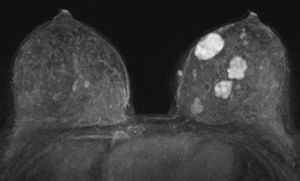

乳腺纖維腺瘤組織切片能顯示乳房各層次結構及腫塊形態、大小及回聲狀況。乳腺纖維腺瘤彩超多為圓形、卵圓形均勻低回聲腫物,多可見光滑清晰的包膜回聲,腫塊後方回聲正常或輕微增強,可見側方聲影,腫塊內可見伴聲影的粗大鈣化。彩色都卜勒顯示腫塊內多無血流信號或見少量血流信號,RI<0.7。

2.乳腺X線攝影

青春期女孩,緻密型乳腺,不適宜進行乳腺X線攝影。中年及以上婦女乳腺X線片纖維腺瘤表現為圓形、卵圓形腫塊,也可呈分葉狀,直徑多為1~3cm,邊緣光滑清楚,與等體積的正常腺體比較,腫塊呈等或稍高密度,周圍可有低密度暈環。部分病灶內可見鈣化,鈣化多位於腫塊中心或邊緣,多呈粗顆粒狀、樹枝狀或斑點狀,也可相互融合成大塊狀,占據腫塊大部或全部,與乳腺癌的成簇沙粒樣鈣化灶不同。